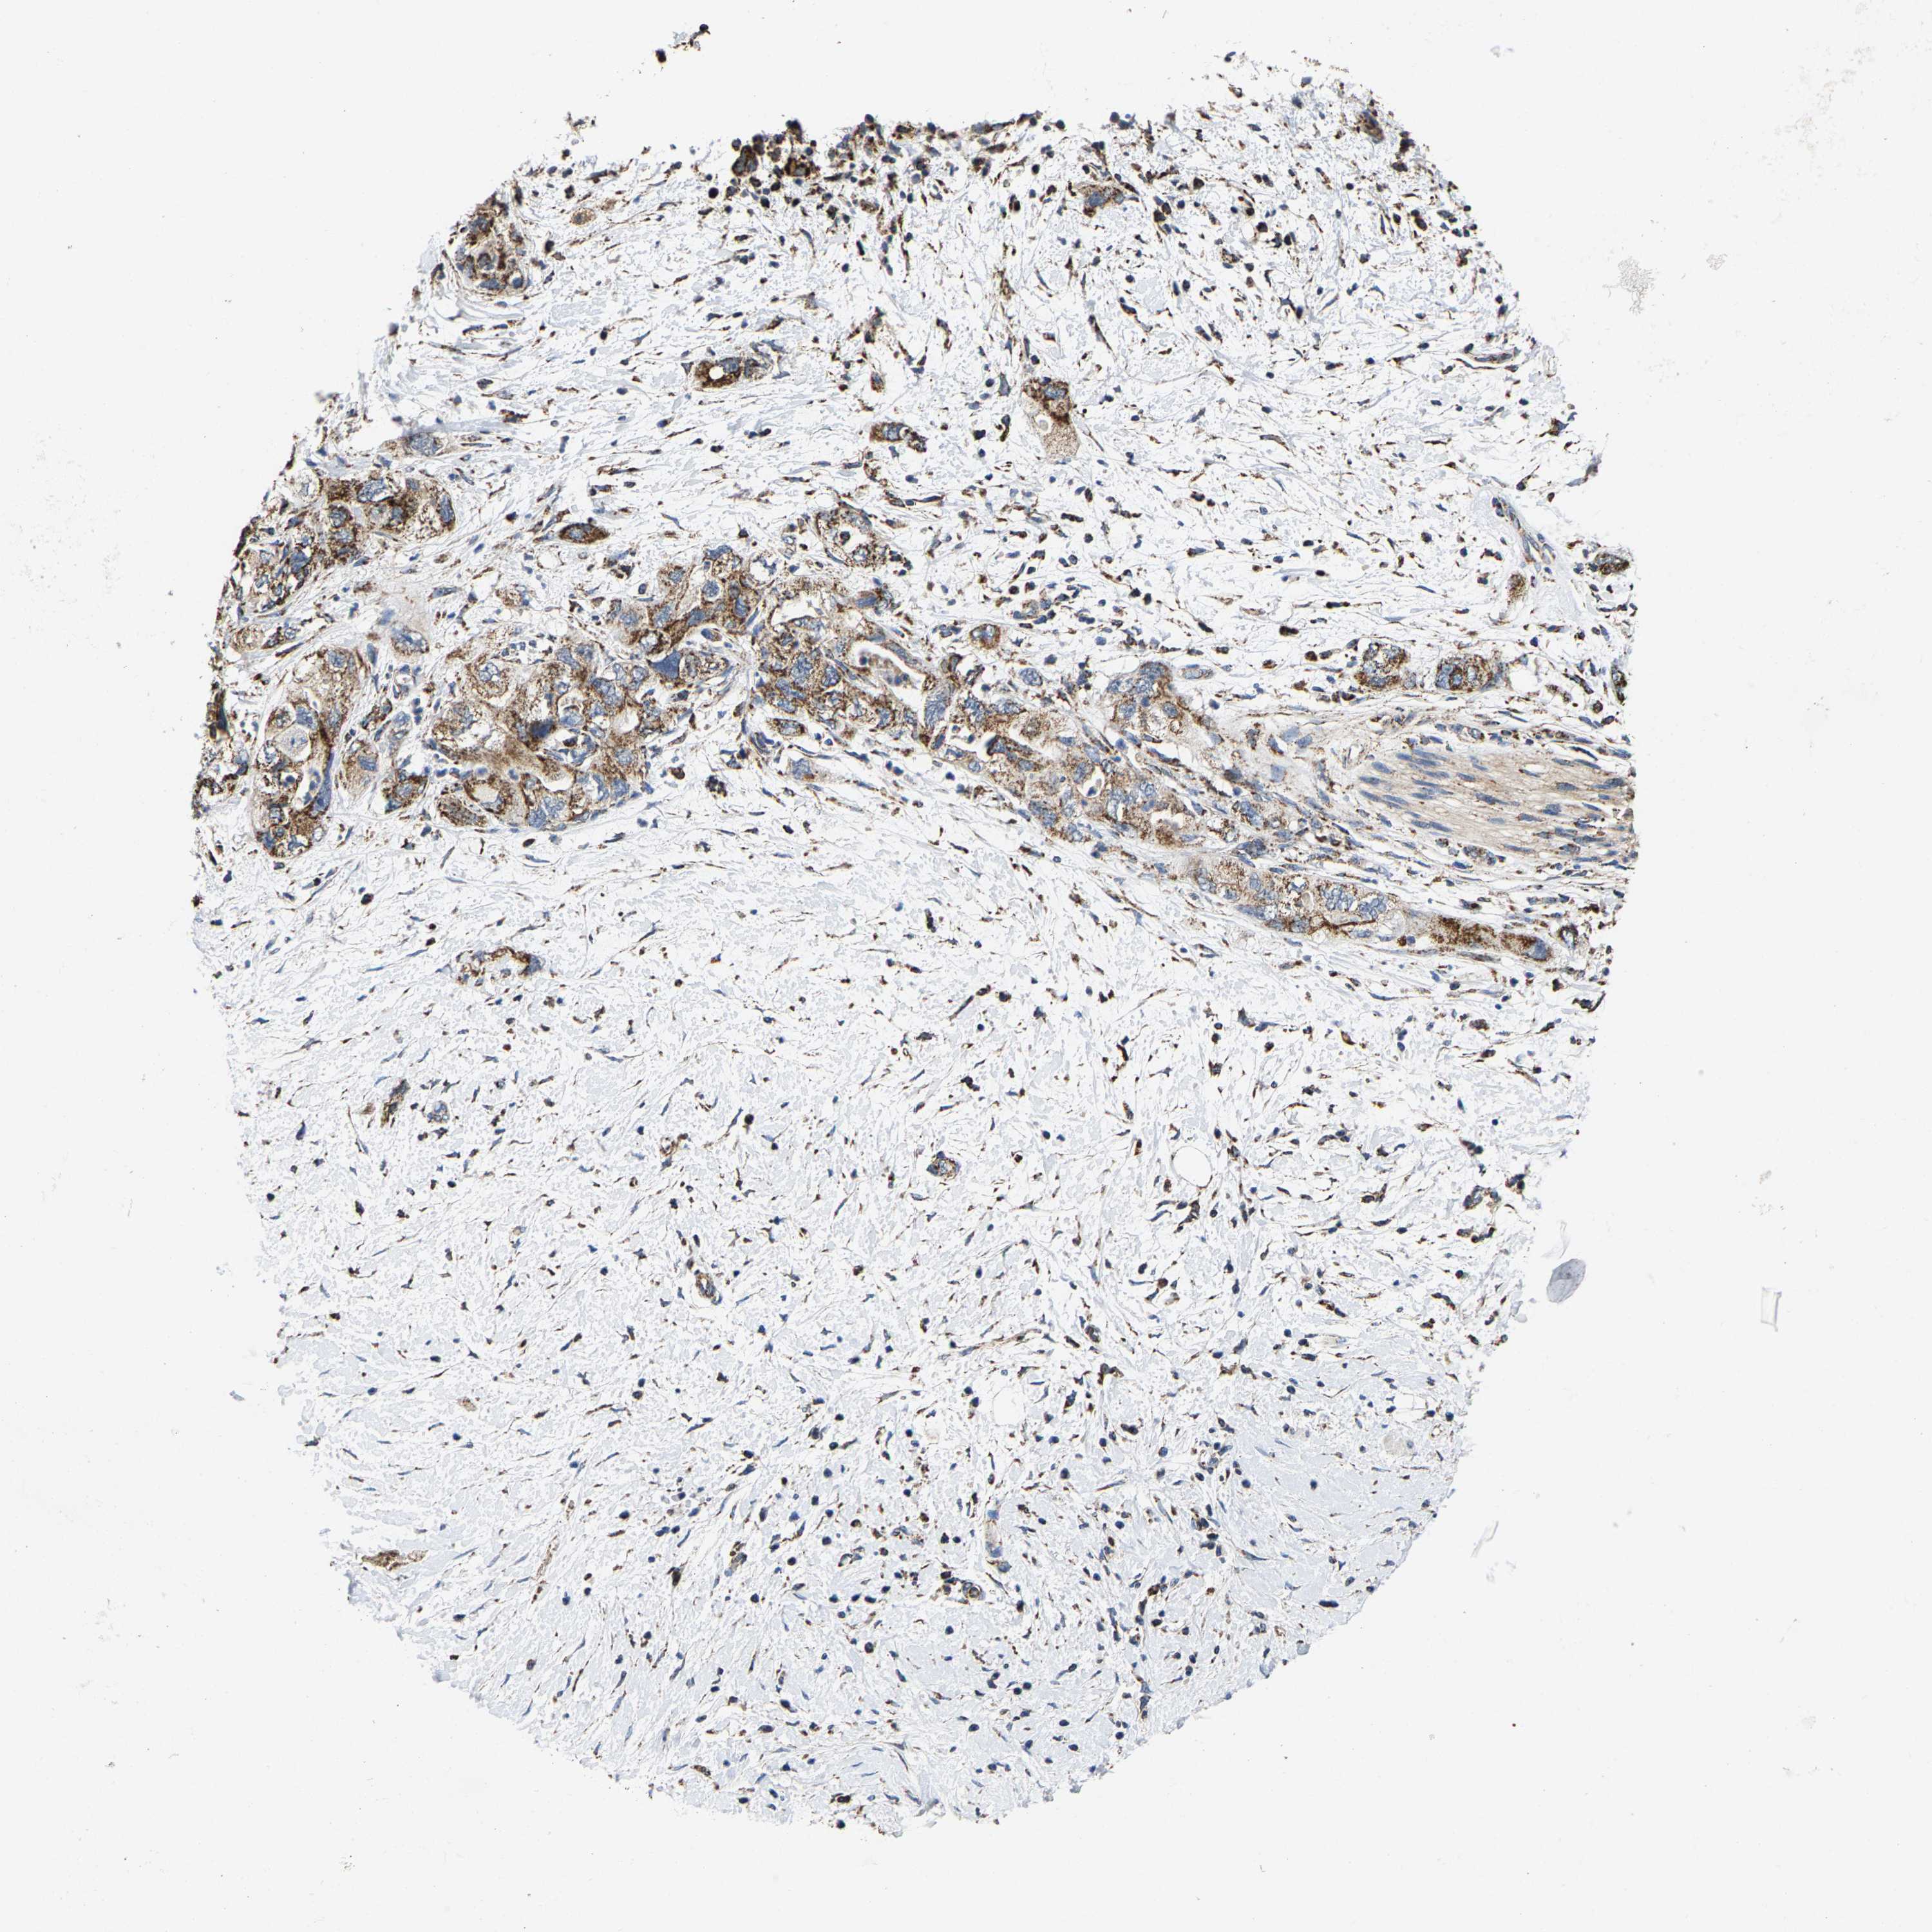

PANCREATIC CANCER - Protein expressioni

A mouse-over function shows sample information and annotation data. Click on an image to view it in a full screen mode. Samples can be filtered based on level of antibody staining by selecting one or several of the following categories: high, medium, low and not detected. The assay and annotation is described here.

Note that samples used for immunohistochemistry by the Human Protein Atlas do not correspond to samples in the TCGA dataset.

Antibody stainingi

Antibody staining in the annotated cell types in the current human tissue is reported as not detected, low, medium, or high, based on conventional immunohistochemistry profiling in selected tissues. This score is based on the combination of the staining intensity and fraction of stained cells.

Each image is clickable and will lead to virtual microscopy that enables deeper exploration of all samples and also displays staining intensity scores, fraction scores and subcellular localization as well as patient and tissue information for each sample.

Antibody HPA020543

Antibody HPA020549

Staining

High

Medium

Low

Not detected

Intensity

Strong

Moderate

Weak

Negative

Quantity

>75%

75%-25%

<25%

None

Location

Nuclear

Cytoplasmic/membranous

Cytoplasmic/membranous,nuclear

Adenocarcinoma, NOS